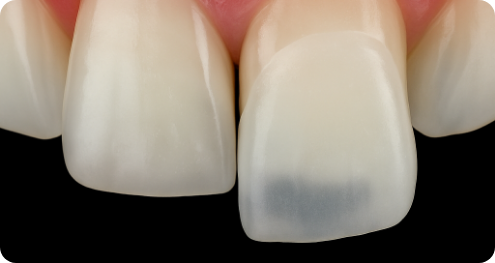

심미보철 진행 후 가장 걱정되는 부분인 변색 부분에서도,

치료 이후 변색과 착색이 적어 오랫동안 높은 지속성을 경험하실 수 있습니다.